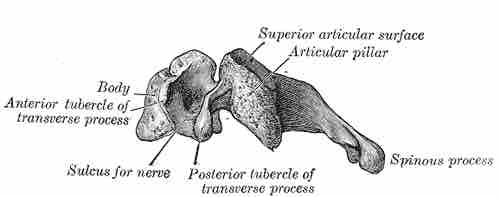

The cervical region of the spine is the most superior and contains seven small vertebrae. The main function of the cervical region is to facilitate attachment of the skull to the spine, protect the spinal cord over the exposed neck and shoulder region, and support the body.

Cervical vertebra, lateral view

The lateral view of a typical cervical vertebra.